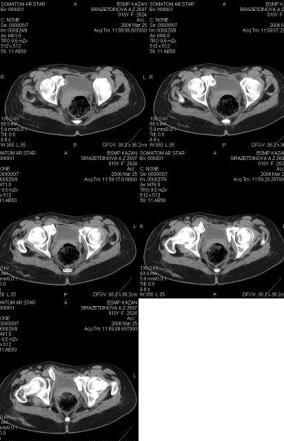

Предоставляю срезы. Если пациентку функционально ничего не беспокоит, стоит ли навязывать ей лечение.

Если пациентка не собирается жить половой жизнью и вообще собирается в моностырь, то пожалуй, я бы согласился с Вами и навязывать лечение не стал.

Но если девочка более активна в жизни, я бы рекомендовал ликвидировать укорочение и вернуть тазу естественную форму.